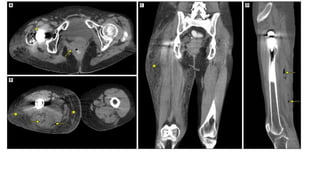

This document discusses necrotizing soft tissue infections such as necrotizing fasciitis. It notes that these infections can originate from trauma, surgery, immunosuppression or malignancy. They can be polymicrobial, involving multiple organisms, or monomicrobial, involving an aggressive single organism. Diagnosis involves history, examination, and imaging tests. Differential diagnoses include deep vein thrombosis, pyomyositis, pyoderma gangrenosum, and cellulitis. Treatment involves stabilization, broad spectrum antibiotics, debridement of infected tissue, and reconstruction.